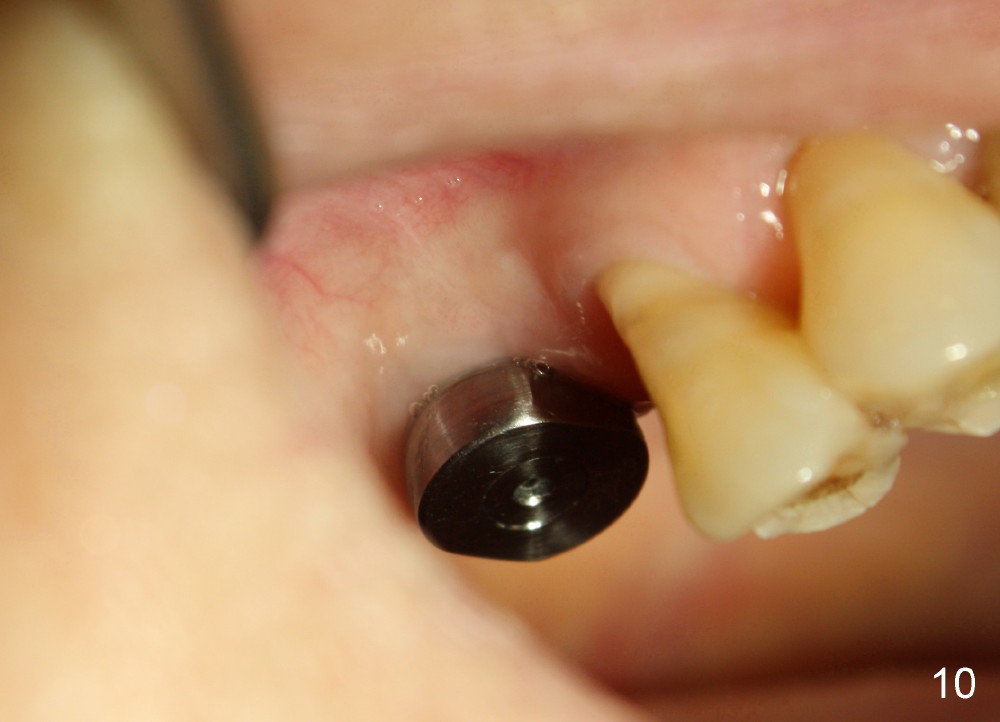

There is no nasal hemorrhage intra or postop. The implant is covered buccally by healing gingiva 7 days postop (Fig.9). It appears that the gingiva has strong regenerative potential. The buccal gingiva looks normal 3 months postop (Fig.10 healing cuff is placed over the implant). The implant appears to have osteointegrated (Fig.11).